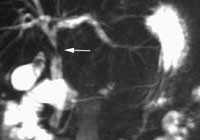

Mistanke om pancreascancer var indikasjonen for S-MRCP hos to. Den ene fikk påvist en stenose i pancreasgangen, med utseende som en svulst, men dette var allerede påvist ved ERCP, og S-MRCP bidrog derfor ikke med ny informasjon. Hos den andre fant man kaliberveksling, best forenlig med pankreatitt. Oppfølging i fem måneder har ikke gitt holdepunkt for malign sykdom. Et stenoserende kolangiokarsinom i ductus choledochus ble også tydeligere fremstilt under sekretinstimulering (fig 3).